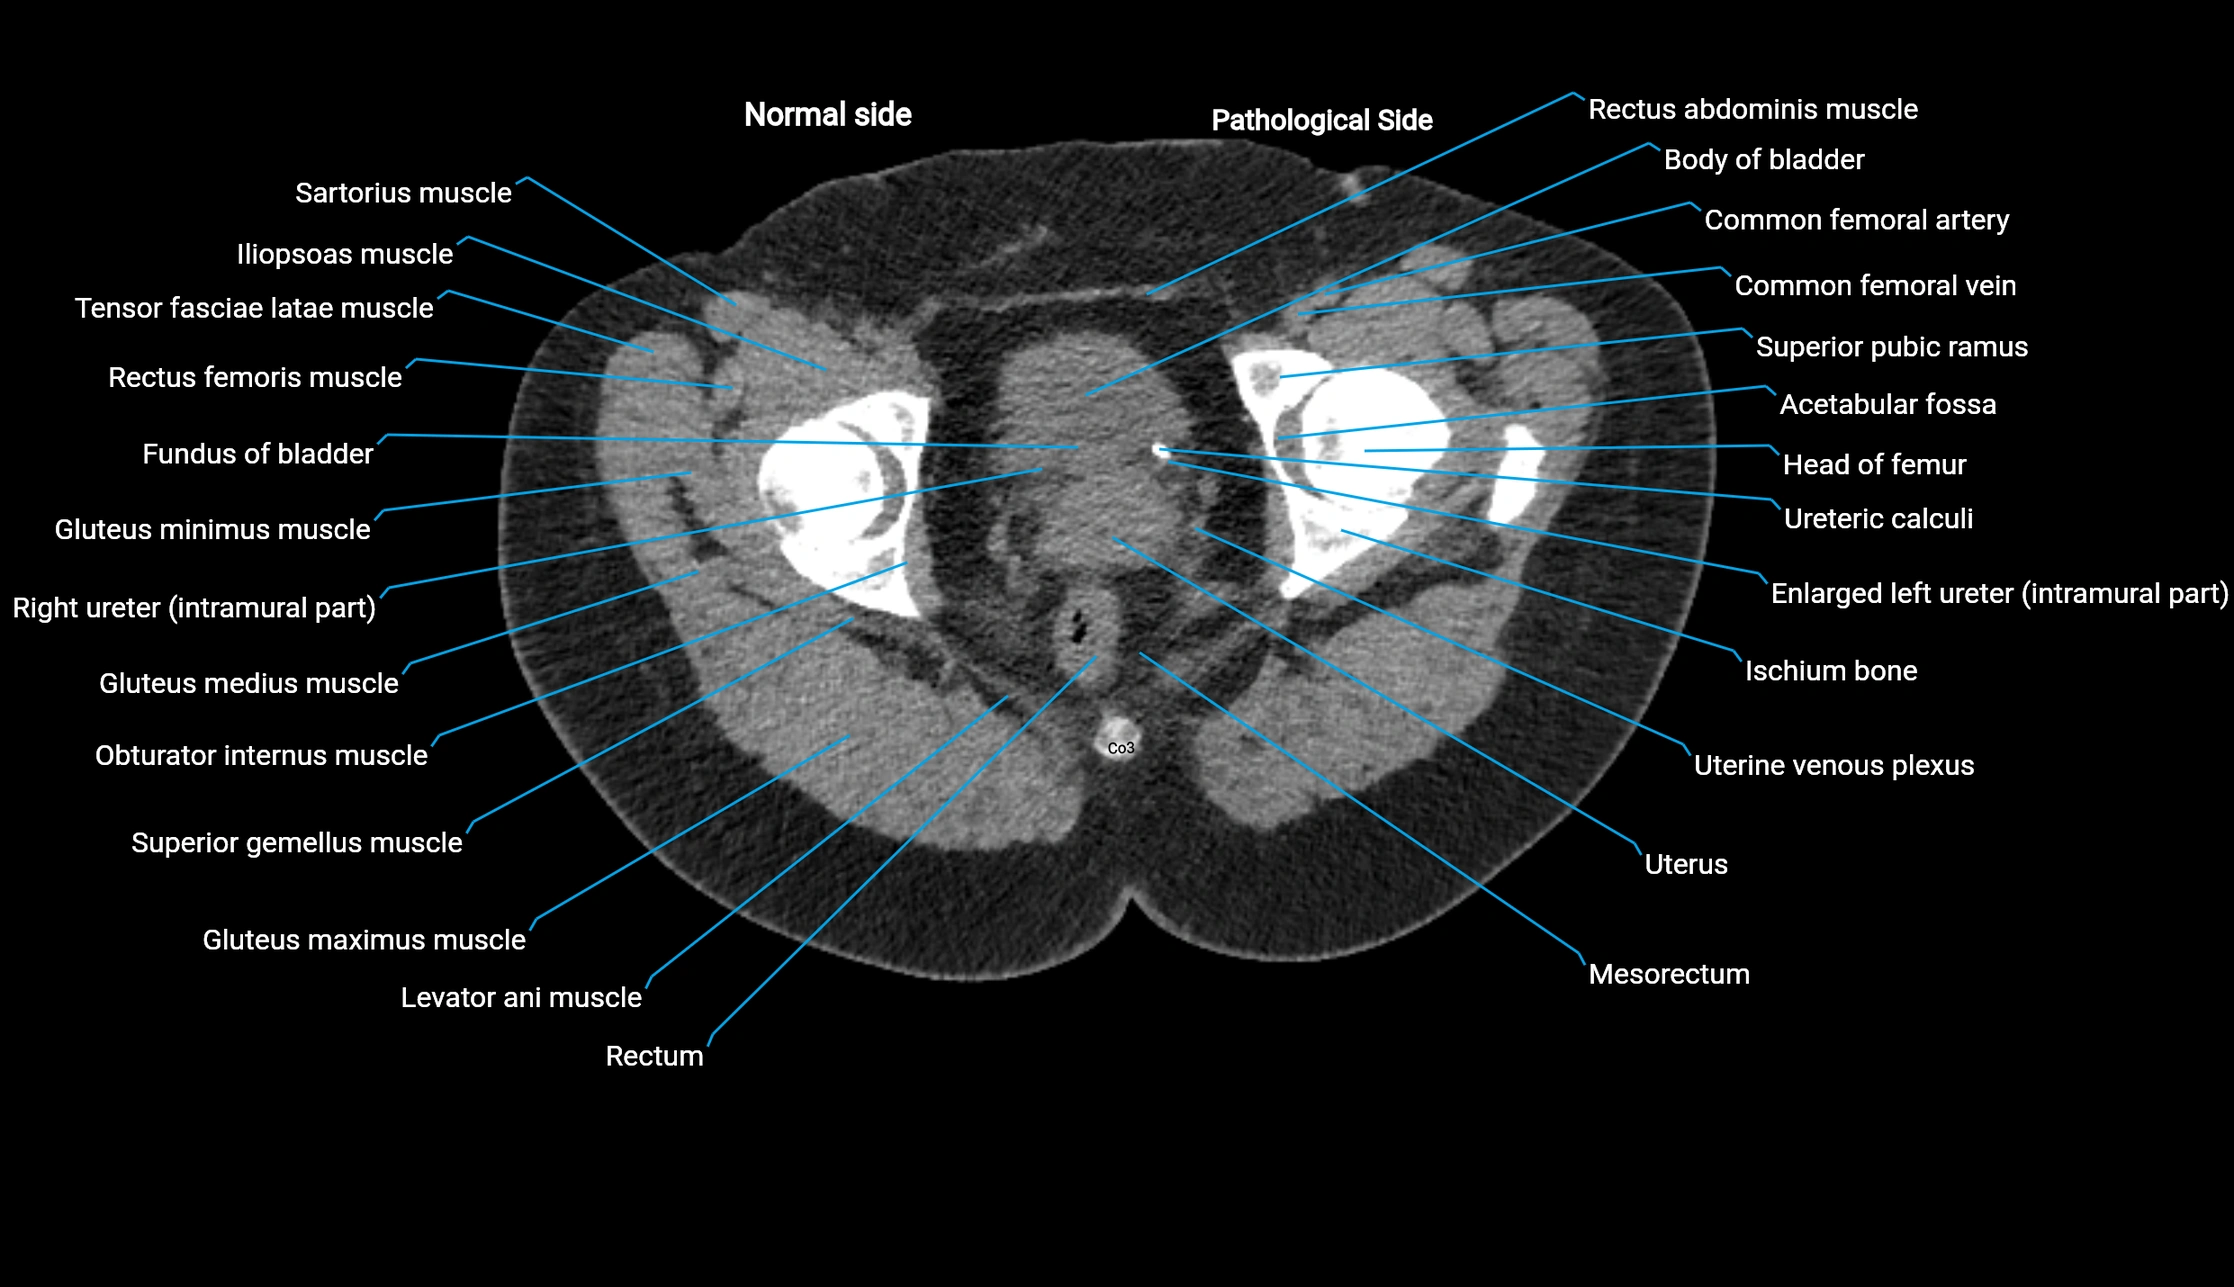

CT Appearance

Non-contrast CT:

• Demonstrates cortical bone of acetabular rim in excellent detail

• Detects fractures, dysplasia, retroversion, or bony overcoverage (pincer impingement)

• 3D reconstructions used in preoperative hip surgery planning

CT Post-Contrast (CT Arthrography):

• Joint contrast outlines the acetabular labrum, cartilage, and margin

• Demonstrates labral tears, cartilage defects, and subtle bony abnormalities

• Alternative to MR arthrography in patients with MRI contraindications